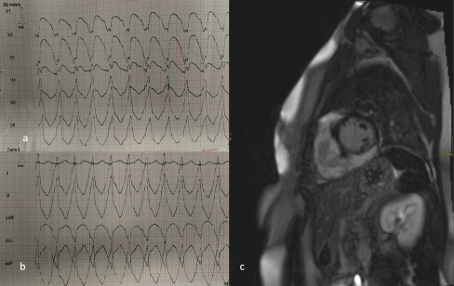

Fallbeschreibung: Eine 39- jährige Patientin ohne kardiale Vorerkrankungen stellt sich dem Rettungsdienst mit einer hämodynamisch wirksamen RVOT-Tachykardie von 220bpm vor. Diese konnte mittels elektrischer Kardioversion erfolgreich terminiert werden. Im 12-Kanal-EKG zeigten sich ein AV- Block I°, unspezifische präterminale T- Negativierungen und ein inkompletter Rechtsschenkelblock. Die Echokardiographie war unauffällig. Eine elektrophysiologische Untersuchung konnte das Anfalls-EKG nicht reproduzieren, jedoch fiel eine erhöhte Vulnerabilität bei Manipulation des RV-Katheters auf mit Auslösung polymoprher nicht-anhaltender VT’s. Im Kardio-MRT zeigte sich ein transmurales Kontrasmittelenhancement v.a. des RV mit „hook- Sign“ und Ödem. Ein low-dose CT des Thorax zeigte keine besonderen Auffälligkeiten. Das durchgeführte 18F-FDG-PET/CT bestätigte den Verdacht einer systemischen Sarkoidose mit vornehmlich kardialer Manifestation. Bei fehlender Lymphadenopathie verzichteten wir auf eine bioptische Sicherung und starteten eine spezifische Therapie mit Cortison, sowie einer antiarrhythmischen Therapie mit Bisoprolol. Die Patientin wurde mit einer Defibrillator- Weste versorgt. Im weiteren Verlauf ist die Implantation eines 2-Kammer-ICD-Systems nach Abklingen der myokardialen Entzündung geplant.

Abbildung 1: a +b) 12- Kanal EKG der hämodynamisch relevanten RVOT Tachykardie, c) Kurzachsenschnitt des Herzens im Kardio- MRT mit typischem „Hook-Sign“ – weitere Abbildungen folgen bei Fallvorstellung.